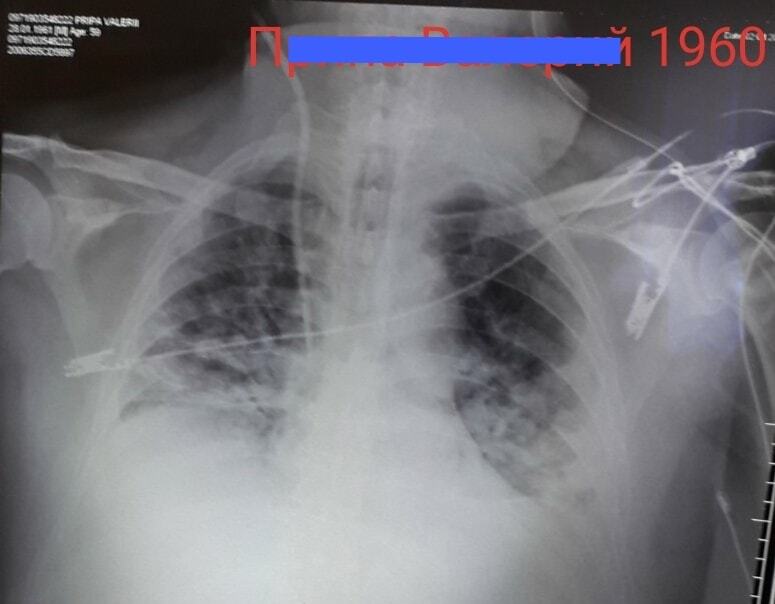

Журналист канала "24 Украина" Андрей Булгаров обнародовал снимки людей, у которых подтверждена коронавирусная инфекция COVID-19.

На снимках, обнародованных на его странице в Facebook, показаны последствия влияния вируса на легкие

"Меня задолбало пояснять на словах всяким неверующим в COVID-19, что все на самом деле очень серьезно. Поэтому попросил папу, который давно на пенсии, но продолжает работать в районной больнице врачом-рентгенологом, прислать мне снимки больных, у которых официально подтверждён COVID-19. В общем, вот как коронавирус постепенно съедает легкие. А если по научному, вызывает двустороннюю полисегментарную пневмонию", – пояснил написал Булгаров.